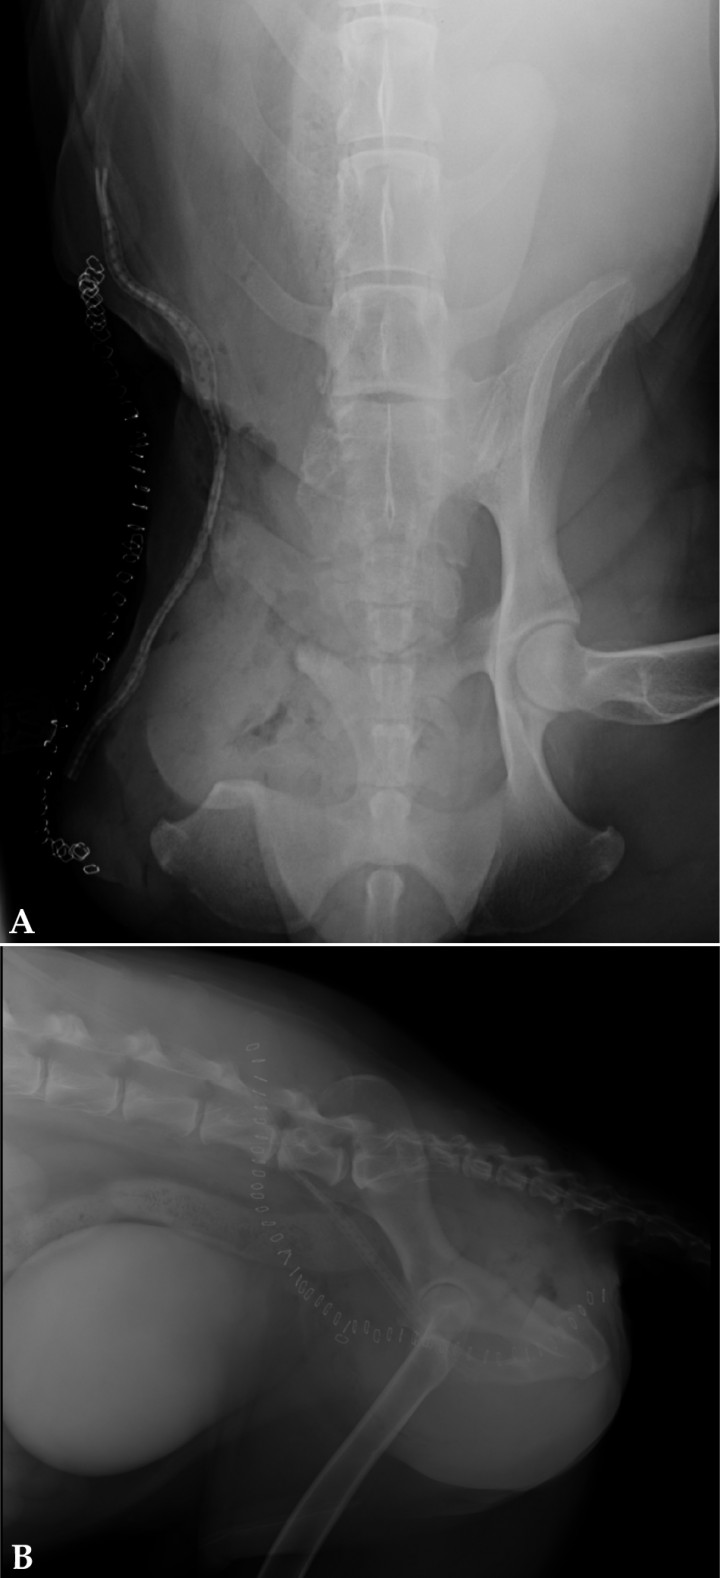

Se procedió a realizar una radiografía de pelvis. (Fig. 1)

Radiografía ventrodorsal de pelvis.

En la radiografía de pelvis se observó una lesión monostótica en el cuerpo del ilion derecho, con un patrón geográfico de osteólisis, pobremente delimitada con interrupción del córtex y reacción perióstica irregular.